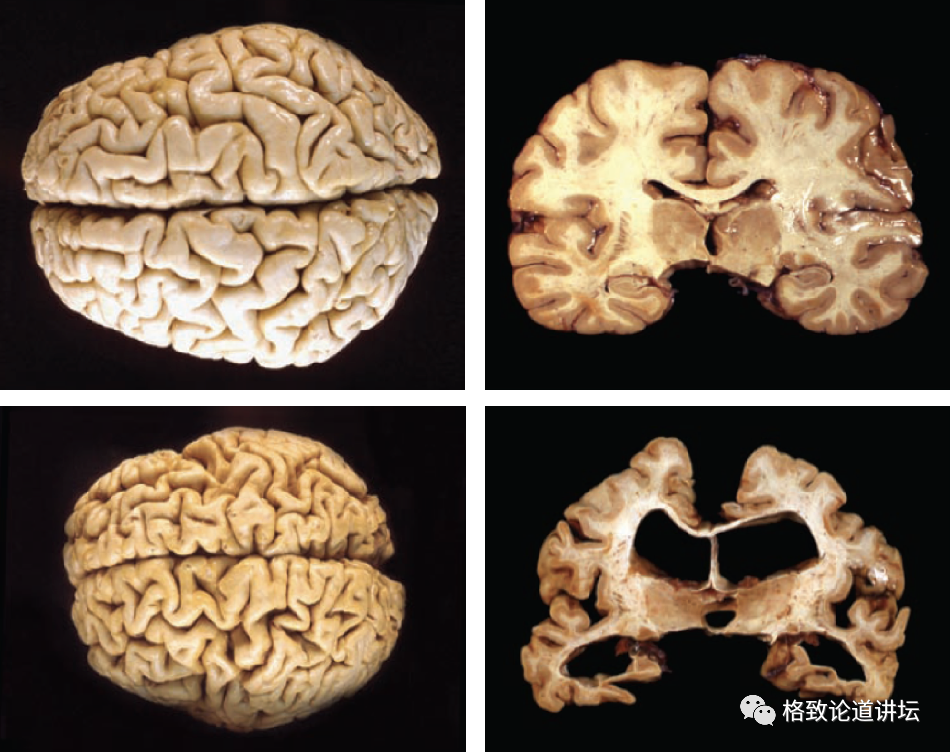

下面的图是老年痴呆病人的脑,可以看到脑的体积已经变小了,有一些脑区已经变空了,没有了。

而这些脑区就是负责学习和记忆的脑区,这就是为什么病人的学习记忆能力没有了的原因。这是一件非常可怕的事情。